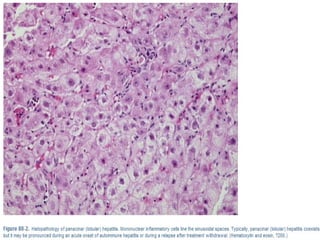

HISTOLOGY

Chronic hepatitis with marked piecemeal necrosis

and lobular involvement

Numerous plasma cells

Interface hepatitis: hallmark finding

Necroinflammatory activity

Evidence of hepatocellular regeneration (“rosette

formation” , regenerative “pseudolobules”)

Bile duct injuries and granulomas are uncommon